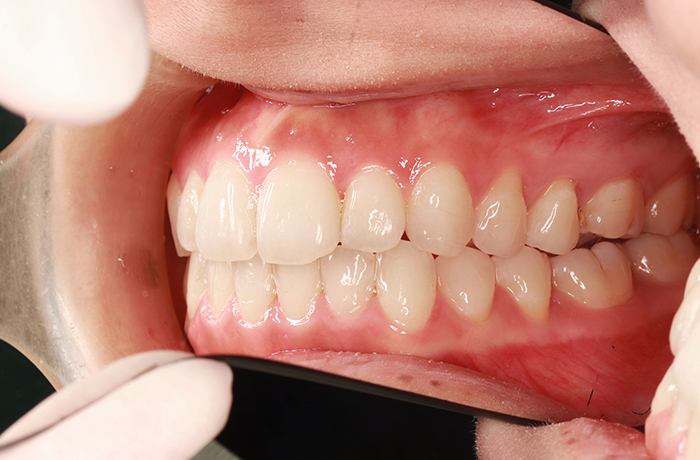

H様

治療前

before

年齢 24歳

性別 女性

治療名称 マウスピース型カスタムメイド矯正歯科装置(インビザライン)・コンプリヘンシブパッケージ(フルパッケージ)

総額治療費用 770,000円(税込10%) 金額備考 精密検査料・診断料 33,000円(税込10%)

治療期間 10か月 通院頻度など 1か月ごと

患者の症状 上顎前歯の前突、開咬、下顎前歯部の空隙

治療方法 非抜歯で、マウスピース型カスタムメイド矯正歯科装置による矯正

上顎臼歯の遠心移動とIPR(歯間隣接面を削合)しました。

治療結果 上顎前歯の前突、開咬が改善されました。